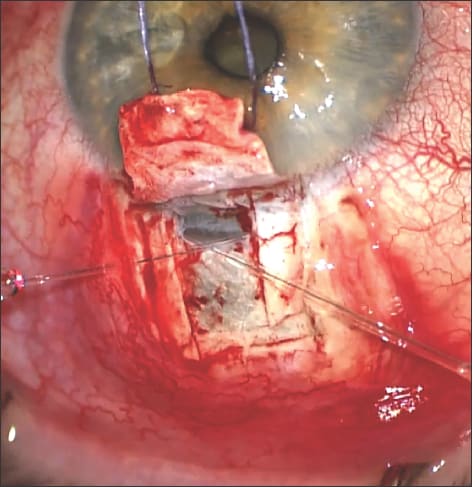

Once the window is created and you have peeled away the outer wall of Schlemm's canal, you sew in a collagen implant, such as the Aquaflow from Staar Surgical shown in Figure 3 below.

Figure 3. Aquaflow collagen implant sutured in place.